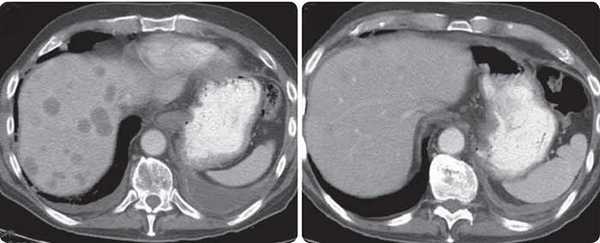

Рак поджелудочной железы с метастазами в печень

Рак поджелудочной железы с метастазами в печень или другие органы соответствует 4 стадии злокачественной опухоли. В четвертой стадии рака поджелудочной железы выделяют две подстадии:

- IVA(локально распространенный рак): отдаленных метастазов нет, но опухоль прорастает в соседние органы, что сильно затрудняет ее хирургическое лечение.

- IVB(метастатический рак): имеются отдаленные метастазы. Чаще всего они находятся в печени.

Помимо печени, опухолевая ткань при раке поджелудочной железы нередко распространяется в легкие, желудок, селезенку, кишечник. Иногда четвертую стадию опухоли удается диагностировать только во время операции.

Если при раке поджелудочной железы обнаруживаются метастазы в печени, прогноз ухудшается. Радикальное хирургическое вмешательство в таких случаях невозможно. Но существуют методы лечения, которые помогают затормозить прогрессирование рака, избавить пациента от мучительных симптомов и увеличить продолжительность жизни.